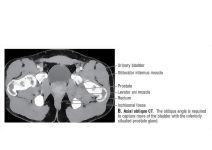

Bladder-Prostate Junction: Axial Oblique CT